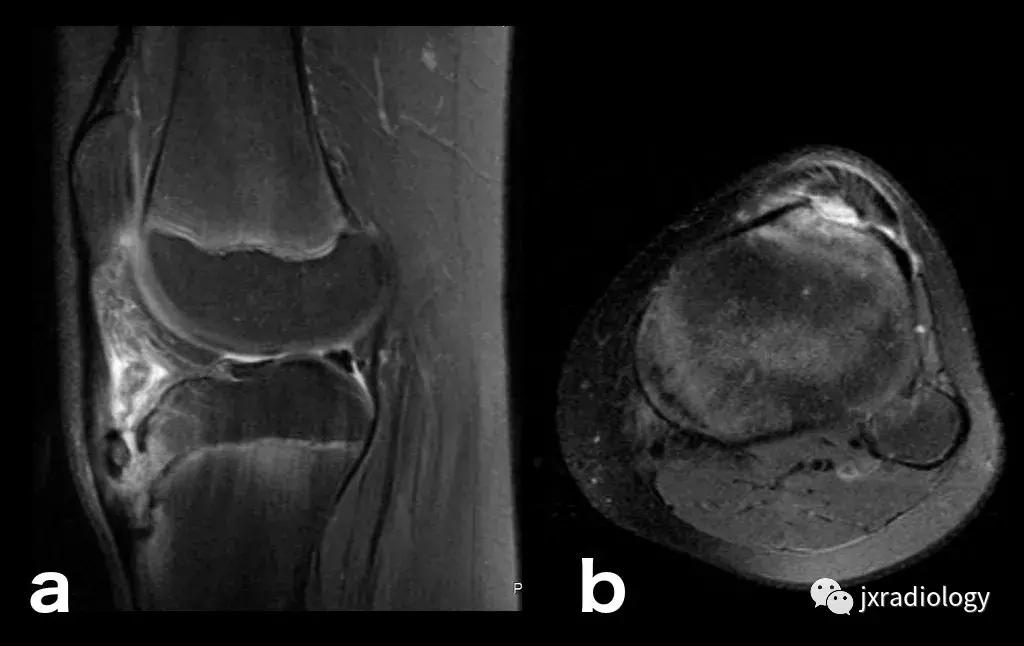

图2:骨性关节炎(OA):男,58岁,股骨内侧髁负重区有软骨缺损,伴有边缘小骨赘和继发性软骨下骨髓水肿。骨性关节炎通常不与创伤性病因分类,而是作为退行性病变分类(a:冠状T1-WI; b:冠状PDWI-FS; c:矢状PDWI-FS)。